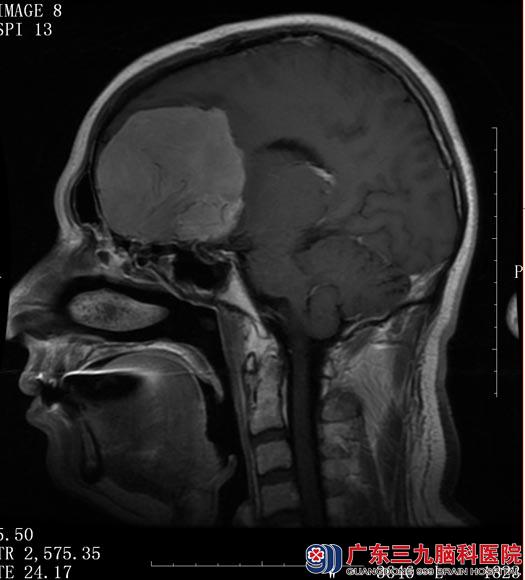

50岁的王先生一向干劲十足。一个月前开始却一改往常,经常出现精神疲倦感,睡眠时间延长,睡眠沉,难以叫醒,同时伴有做事兴趣下降,难以兴奋,近期记忆力也开始下降。以为是春困,按土方法喝祛湿汤,但症状没有改善。当地医院行头颅CT检查提示左侧额叶巨大占位。广东三九脑科医院进一步MR检查提示:左侧额叶病变大小约74.1mm×56.2mm×63.1mm,建议手术切除。

▲MR检查